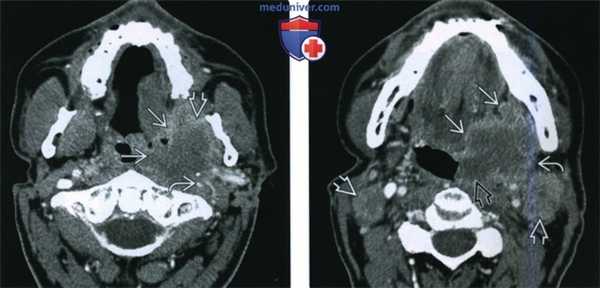

(Слева) При аксиальной КТ с КУ визуализируется объемное образование (инфильтративный ПКР), распространяющееся в жевательное пространство, окружающее и сдавливающее левую внутреннюю сонную артерию, что является признаком стадии Т4b. Был выявлен белок р16 - маркер вирусной инфекции (ВПЧ).

(Справа) При аксиальной КТ с КУ на более каудальном уровне визуализируется опухоль миндалины (ПКР), распространяющаяся кпереди в полость рта, а также вдоль задней стенки ротоглотки до средней линии. Наличие увеличенных и некротически измененных лимфоузлов уровня IIА означает стадию N2c.